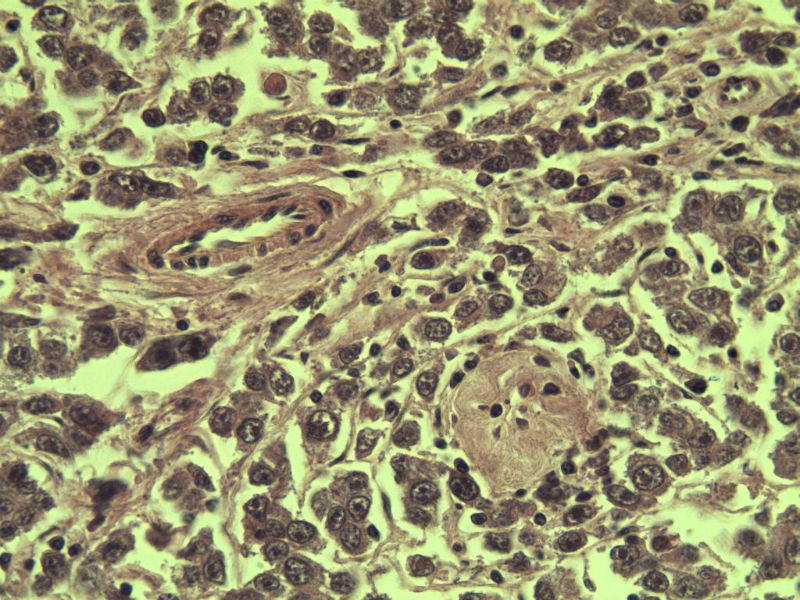

男 27岁 腹腔隐睾 5*3*2 cm, 切面灰红灰黄、实性、质中,请各位老师看看,是精原细胞瘤吗?感觉不像.腹腔隐睾图1

典型的精原细胞瘤,隐睾易恶变